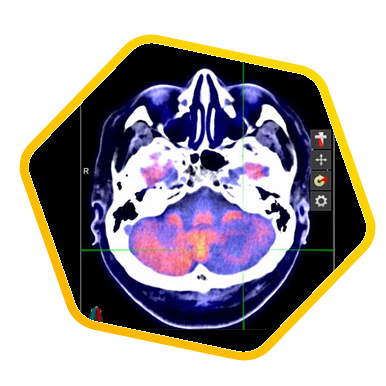

PET/CT scans with special tracers can show 3-dimensional images of blood flow and biomolecules deposition in the brain for diagnosis and monitoring the therapy progress of various neurological diseases, such as Alzheimer's, Dementia, Parkinson's disease, Huntingdon's chorea and autism. In 2018, the National Institute on Aging-Alzheimer's Association (NIA-AA) had revised the definition of Alzheimer's Disease (AD) from a syndrome diagnosed by a set of clinical criteria to a biological construct using abnormal protein deposits to define AD as a unique neurodegenerative disease that can lead to dementia. Our hospital has almost 20 years of experience in producing specific tracer to detect abnormal protein deposition in the brain.

For some types of epilepsy patients, PET/CT scans can localize the epilepsy-causing focus in the brain. Modern stereotaxic neurosurgery can then cure epilepsy permanently by excising the focus.